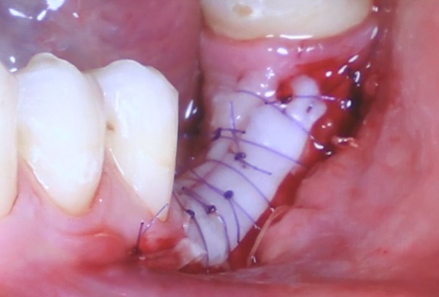

Technique opératoire étape par étape

Cette partie constitue le cœur de la formation. À travers deux cas cliniques détaillés, schémas explicatifs et vidéos, nous verrons chaque étape du protocole opératoire : design du site receveur, prélèvement palatin, adaptation de la greffe, sutures et prise en charge post-opératoire. Nous analyserons les avantages, limites et points de vigilance de la technique. Un focus particulier sera fait sur l’attache rampante, sa dynamique et son rôle dans la cicatrisation tissulaire. L’objectif est de fournir un protocole clair, reproductible et sécurisant.